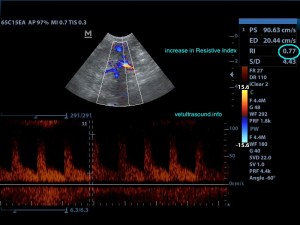

Ευρήματα: Στον υπέρηχο κοιλίας βρέθηκε επώδυνη διόγκωση και των δύο νεφρών με πάχυνση της φλοιώδους ουσίας, η οποία παρουσίαζε έντονη ανομοιογένεια. Οι νεφρικές πύελοι ήταν ήπια διατεταμένοι και στο εσωτερικό τους παρατηρήθηκε αφθονία ιζήματος. Οι ουρητήρες, οι οποίοι ήταν επίσης διατεταμένοι, απεικονίζονταν μέχρι την είσοδό τους στην ουροδόχο κύστη. Αφθονία ιζήματος βρέθηκε στην ουροδόχο κύστη. Η εικόνα αυτή είναι συμβατή με διάμεση νεφρίτιδα και στην συγκεκριμένη περίπτωση με πυοκοκκιωματώδη φλεγμονή των νεφρών, συνεκτιμώντας τα εργαστηριακά ευρήματα, τον έντονο πόνο και τη διάταση των ουρητήρων. Το resistive index ( δείκτης αγγειακής αντίστασης) βρέθηκε αυξημένο (0.77) σε μεσολόβιο αρτηρίδιο του νεφρού. Φυσιολογικά θα έπρεπε να είναι (0.6±0.06). Αυτό δείχνει πως το οίδημα του νεφρικού παρεγχύματος εξαιτίας φλεγμονής ή οποιαδήποτε άλλης διήθησης, νεοπλασματικής ή μη, πιέζει τα αγγεία και αυξάνει την αντίσταση του αίματος προς το νεφρό. Ένα επιπλέον διαγνωστικό βήμα για την διερεύνηση της αιτίας, για την αποτελεσματικότερη θεραπεία και την εγκυρότερη πρόγνωση, είναι η λήψη κυτταρολογικού υλικού από το νεφρικό παρέγχυμα και ούρου από τη νεφρική πύελο για καλλιέργεια, στα οποία ο ιδιοκτήτης δεν θέλησε να προχωρήσει.